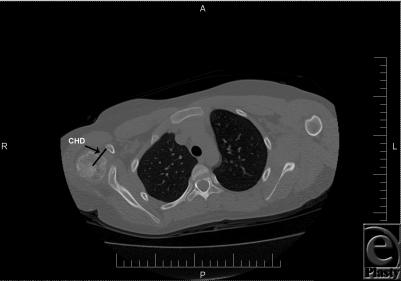

Twenty patients with deformities secondary to obstetric brachial plexus injury were included. Coracohumeral distances were measured on computed tomographic images. Clinical functioning was evaluated through video recordings by using a modified Mallet scale. Paired Student t tests were used to determine statistical significance of anatomic and functional parameters, pre- and postoperatively.

纳入20例继发于产瘫臂丛神经损伤的畸形患者。在计算机断层扫描图像上测量喙肱距离。通过使用改良的马利特量表的视频记录来评估临床功能。采用配对学生t检验来确定术前和术后解剖学和功能参数的统计学意义。